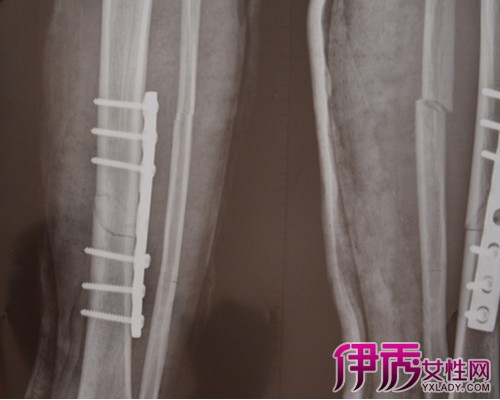

1.发现骨折之后要第一时间去附近的医院骨科就诊,不能强忍拖延。到医院骨科拍张X光片子看一下,拍片的目的是为了看下是什么地方骨折,是一处骨折还是多处骨折,再根据骨折的情况进行治疗。